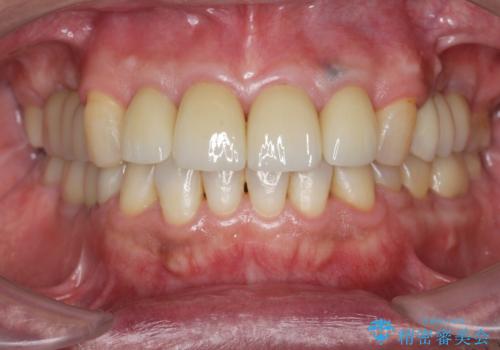

かぶせものと歯ぐきの境目が黒い 40代女性

保険のかぶせ物・詰め物を金属を使わないセラミックへ 自然な見た目へ